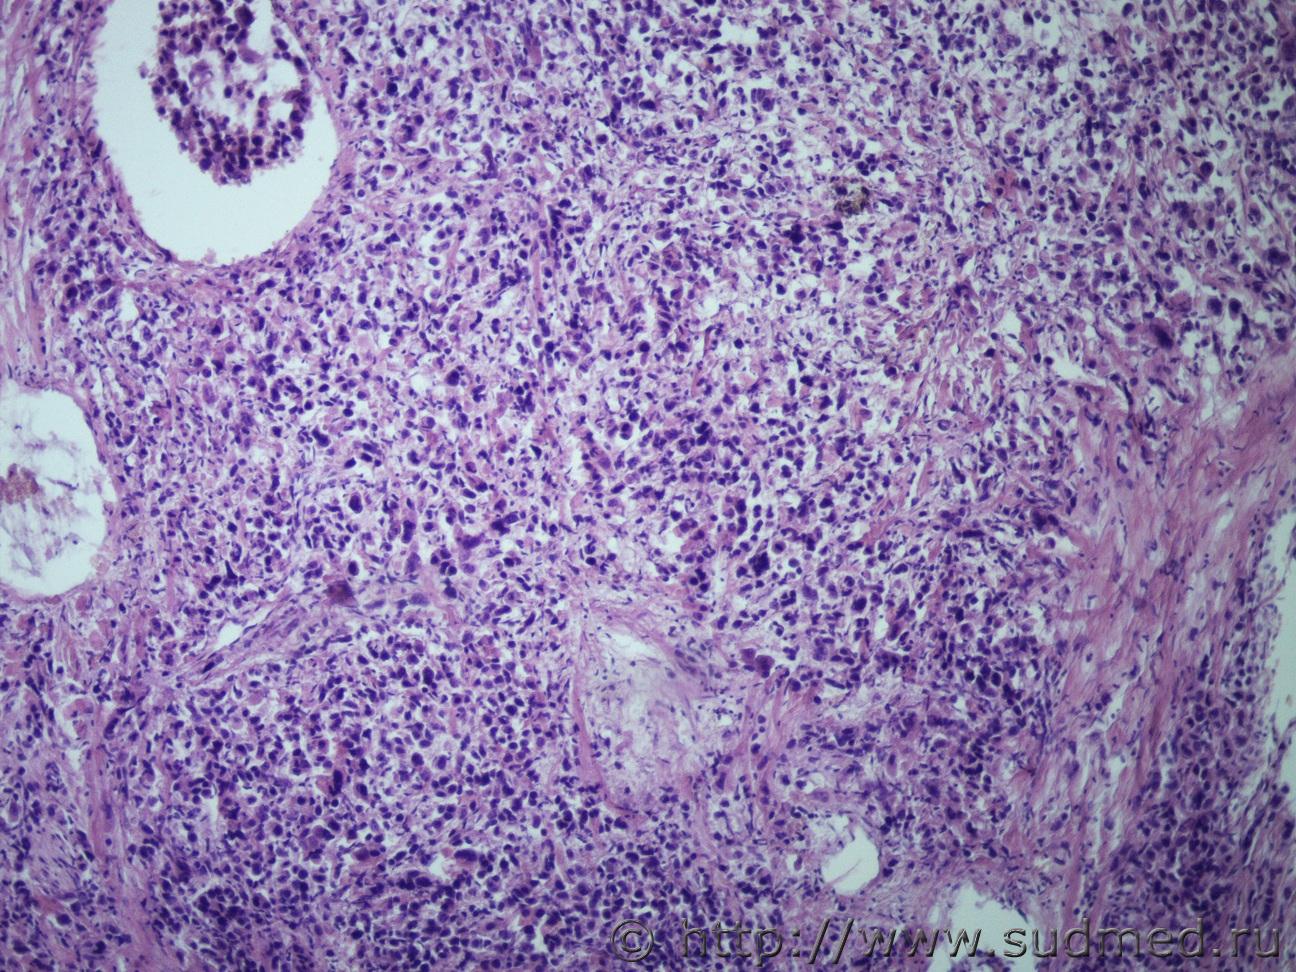

Метастазы в печени |

IVANNES Метастазы в печени 4.10.2019 - 09:53

Anton Вполне можно. ПКР. Особенно если добавить окраску ... 4.10.2019 - 13:08

IVANNES Вполне можно. ПКР. Особенно если добавить окраску ... 4.10.2019 - 14:03

Anton Что может быть скромнее альциановой синьки. Только... 4.10.2019 - 14:09

IVANNES Что может быть скромнее альциановой синьки. Только... 4.10.2019 - 14:30

Медик Перстневидноклеточный рак. 5.10.2019 - 18:50

доктор морфолог Коллоидный( слизистый рак) , либо аденкарцинома с ... 7.10.2019 - 13:15![]() ![]() |